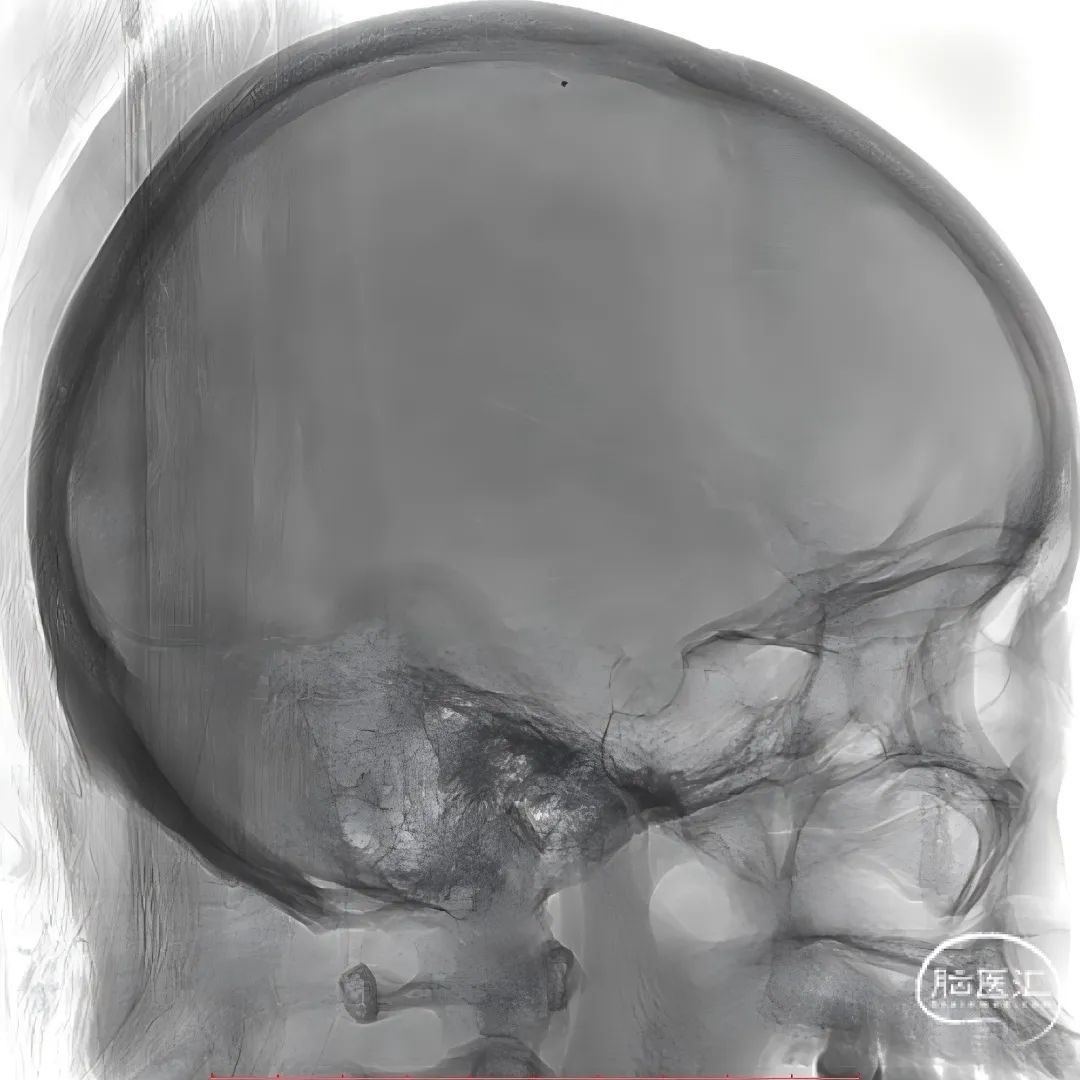

术前CT:左侧颞叶低密度病变考虑梗死灶,后续梗死灶不断增大合并出血。

术前CTV:左侧颈内静脉、乙状窦、横窦闭塞,血栓形成。

术前复查头部CT。

股动脉穿刺置5F鞘做静脉窦造影,股静脉穿刺置8F鞘进行治疗。260cm泥鳅导丝,将132cm 0.068" React™导管送至上矢状窦前部,尽量推高长鞘,增加支撑力。

经中间管手推造影,确认血栓位置。